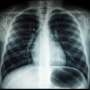

Lung cancer mortality rates among women in the European Union (EU) are projected to stabilize by 2026, following over 25 years of continuous increases. This trend reflects significant public health changes and advancements in cancer awareness, prevention, and treatment across the region.

The shift in lung cancer death rates among women signifies a crucial turning point in public health efforts. Historically, lung cancer has been one of the leading causes of cancer-related deaths among women in the EU, largely attributed to smoking rates that surged in previous decades. However, increased awareness of the dangers of smoking and enhanced screening and treatment options have contributed to this positive change.